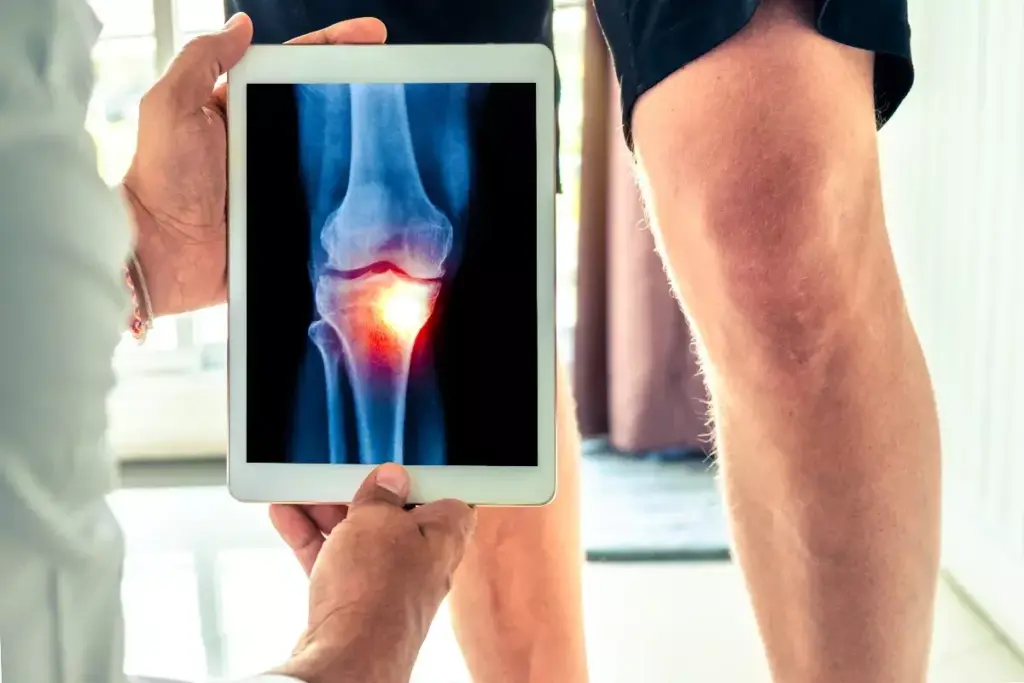

Doctors with special skills in MRI read these images. They decide on medicines, injections, or therapy. For example, a knee MRI shows how bad the damage is. This helps doctors make a treatment plan just for you.

What does a knee MRI look like with arthritis?

A knee MRI with arthritis may show narrowed joint spaces, cartilage thinning, bone marrow lesions, synovial inflammation, and sometimes fluid accumulation. It highlights both bone and soft tissue changes.